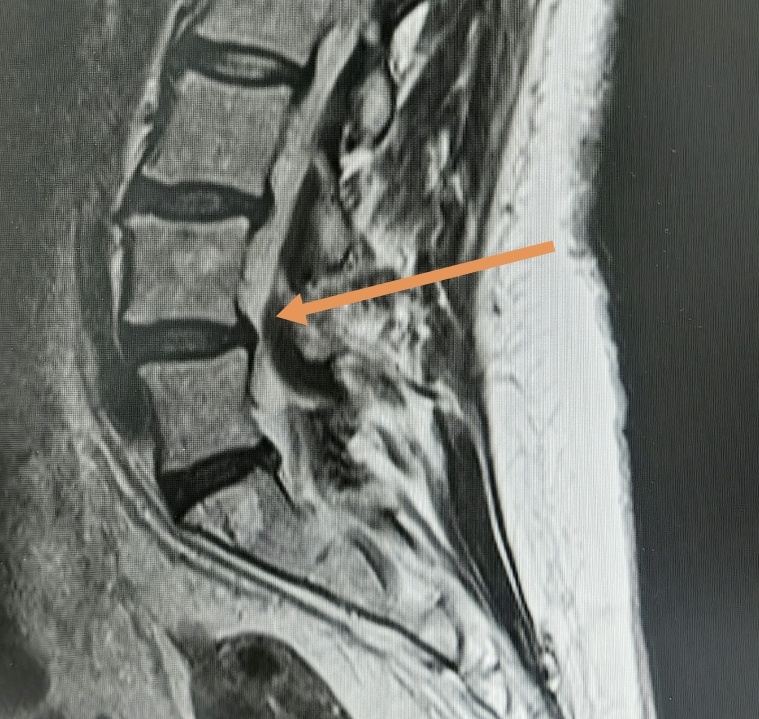

Теперь уже пациентка обратилась для выполнения МРТ, где был выявлен стеноз позвоночного канала на уровне L4-L5 уровня (сужение до 8 мм).

Как видно на изображении, диск выступает незначительно, а стеноз канала обусловлен гипертрофией жёлтых связок. Темная масса под стрелкой.